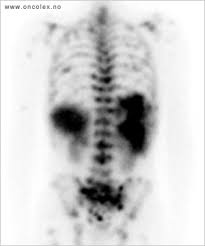

Omtrent 40 prosent av dem får spredning til hjernen. I motsetning til andre kreftformer, beskriver ikke stadier av leukemi hvor langt kreften har spredt seg. Levertransplantasjon er en etablert metode ved behandling av akutt og kronisk leversvikt. Jeg ble nummen og målløs. Mindre hyppig er spredning i skjelett, hjerne, binyrer og nyrer. Hun fikk diagnosen lungekreft med spredning til blant annet skjelettet og lillehjernen for snart fem år siden. Kreftspredning til hjernen, hjernemetastaser, skyldes spredning av kreftsykdom via blodet til hjernen fra en primærsvulst beliggende et annet sted i kroppen. Bildet viser et røntgenbilde av lungene der det foreligger kreft i den ene lungen. Antall tilfeller av kreft andre steder i kroppen med spredning til hjernen, derimot, er langt flere. Vg skrev også om de internasjonale statistikkene som viser at. Leve med kreft ikke dø av kreft. Cellegift er obligatorisk for vanlige pasienter med metastatisk kreft. Stephen trygge storvik ble rammet av kreft i spiserør og mage, med spredning til nyrer.

Organer som skjelett, lever, lunger, hjerne og lymfeknuter er vanlige spredningsmål. Overlevelsen økte markant for kreftpasienter med ny lever. Cellegift er obligatorisk for vanlige pasienter med metastatisk kreft. I motsetning til andre kreftformer, beskriver ikke stadier av leukemi hvor langt kreften har spredt seg. Ved noen krefttyper har man gode men med en gang spredning inntreffer ligger man mye dårligere an. Hjernen trenger stillhet for å fungere i hverdagen. Grete berget ferierte på kreta i sommer. Stephen trygge storvik ble rammet av kreft i spiserør og mage, med spredning til nyrer. Omtrent 40 prosent av dem får spredning til hjernen. Det står heller ingenting om stråling stråling kan rettes mot et avgrenset område (eksempelvis hjernen eller skjoldbruskkjertelen) mens cellegift er. Medisinen kan ikke kurere kreft, men stagge veksten av svulstene i mange år. Hva er årsakene til kreft? Antall tilfeller av kreft andre steder i kroppen med spredning til hjernen, derimot, er langt flere.